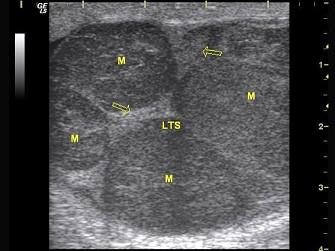

问题 男性,32岁,超声示睾丸内可探及多个结节状低回声光团,边界清,CDFI:血流信号丰富。如图所示,考虑为?(?)

选项 A.睾丸脓肿 B.精原细胞瘤 C.睾丸炎 D.睾丸结核 E.睾丸恶性畸胎瘤

答案 B